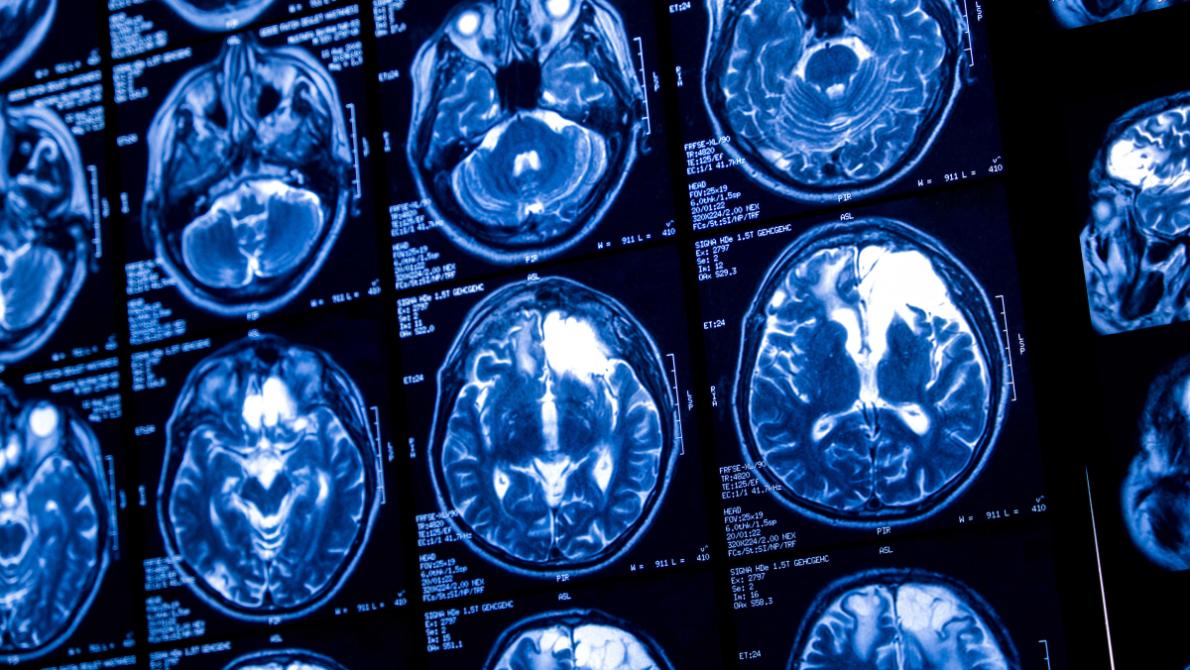

Regardless of tumor grade, patients benefit from regular follow-up care and imaging to monitor for recurrence or progression. MRI scans are commonly used to assess whether treatment is working and to detect changes in the tumor’s behavior.